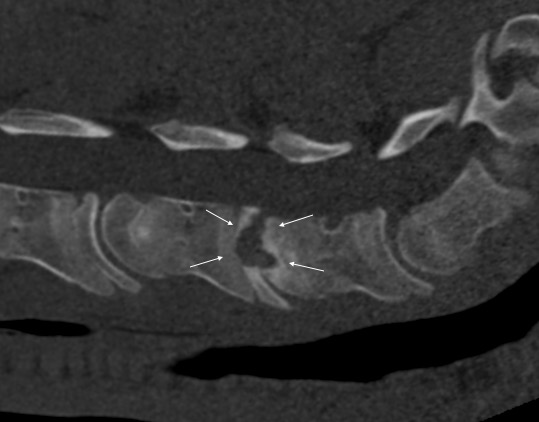

Pokud neurologické vyšetření potvrdí ataxii (stupeň 1–5), je potřeba stanovit její přesnou příčinu. Nejčastěji se jedná o zúžení páteřního kanálu v oblasti krčních obratlů, kde pak dochází k útlaku míchy – Wobblerovu syndromu. Existují ale i další příčiny ataxie, které je potřeba vzít na vědomí, například vrozené abnormality krčních obratlů (vertebrální malformace), úrazy krční páteře, nádory, virové infekce (EHV), bakteriální infekce (abscesy, záněty meziobratlových plotének a kostí) (obr. 2a, b, c), parazitární infekce nebo některé toxiny.

Obrázek 2a, b: Hříbě s ataxií a horečkou způsobenou zánětem kostí obratlů C6–C7. Na CT je jasně patrné výrazné poškození kostí v důsledku infekce (bílé šipky). Na obrázku 2b je stejný případ z jiného pohledu